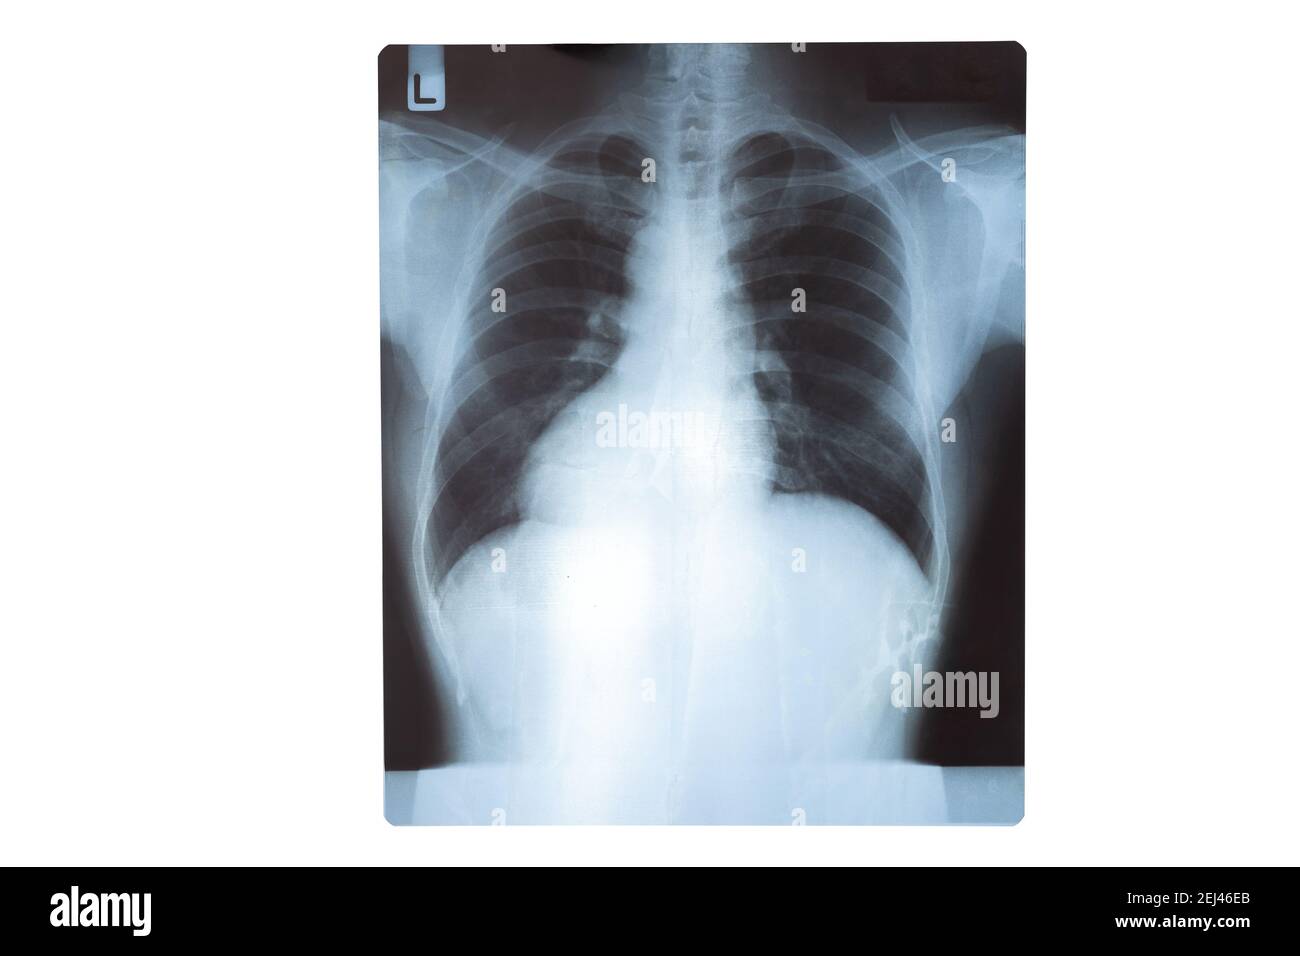

From klavtdhib.blob.core.windows.net

Chest X Ray Healthy Lungs at Rosner blog Do All Chest Infections Show Up On Xray In fact every radiologst should be an expert in chest film reading. Imaging plays an integral role in the diagnosis and management of suspected pulmonary infections and may reveal useful signs on chest radiographs and ct scans. Blood tests and phlegm (sputum). These white spots indicate that the alveoli are filled with pus. Acute chest infections (lower respiratory tract infections). Do All Chest Infections Show Up On Xray.